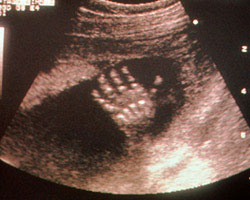

O bebé na ecografia: imagens e vídeo, semana 21

Se queres saber como é o teu bebé às 21 semanas de gestação, não percas o vídeo e as imagens te oferecemos em seguida. Surpreende-te!

Ecografia de 21 semanas